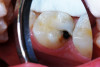

(1.) Hypocalcified/carious first molar, 12 months after SDF application.

Figure 1

SDF was developed in Osaka, Japan, in 1969.24,25 During the next 5 decades, its use and related research spread around the world.26-32 Various formulations of SDF (Bioride®, Densply Industria e Comericio Ltda; e-SDF, Kids-e-Dental Llp; Riva Star, SDI; Saforide®, Toyo Seiyaku Kasei Ltd) have been developed in different countries to attenuate dental caries infections. In 2014, an SDF solution made up of 62% water, 25% silver, 8% ammonia, and 5% fluoride (Advantage Arrest® Silver Diamine Fluoride 38%, Elevate Oral Care, LLC) was the first to gain approval by the US Food and Drug Administration to be used in the United States as a tooth desensitizing agent33; however, others have since been cleared as well. Its ability to affect dental caries pathodynamics has developed into an exceedingly popular off-label use by dentist clinicians. Figure 1 depicts an example of a malformed and carious permanent first molar that had been treated with SDF followed by 2.5% sodium fluoride varnish 6 months and 12 months prior when it was only partially erupted. This strategy attenuated the caries infection for over a year, until the patient, an extremely anxious 7-year-old boy, was able to tolerate routine restorative treatment.